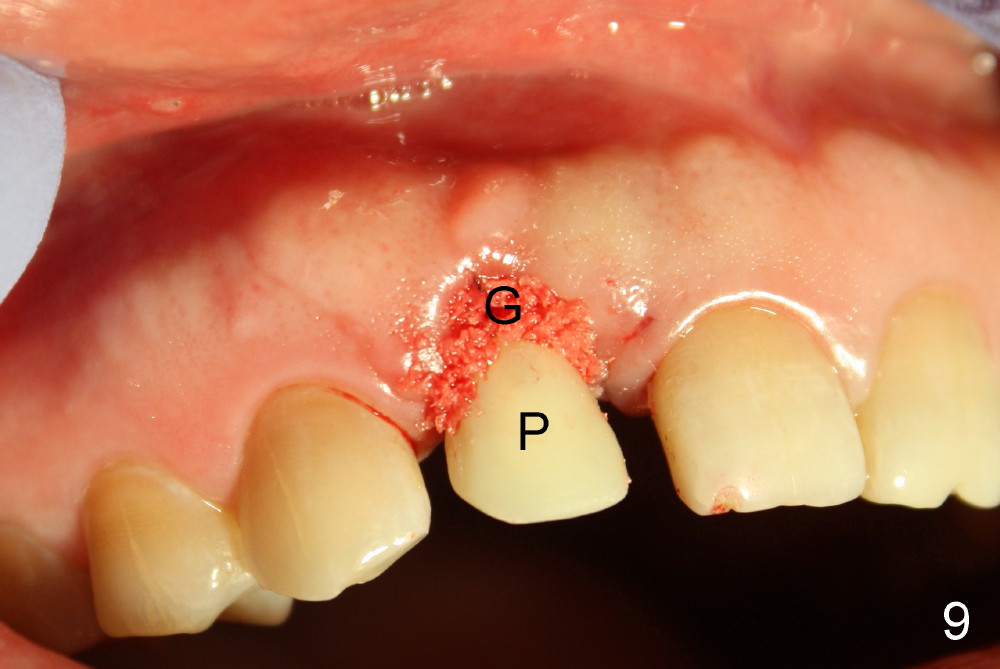

Malpositioned implant in the anterior region is cosmetically unacceptable. Immediate provisional allows us to note the issue immediately. The crown looks too long. Secondly, the provisional is easily dislodged, since the buccal aspect of the angled abutment is over trimmed (Fig.1). The implant (3.8x14 mm), which has been placed 3.5 months, is unexpectedly easily removed by reverse torque (Fig.2). The buccal wall is intact, whereas there seems to be enough bone lingually to place an implant. A small incision is made (Fig.11) so that the gingival tissue can be transferred buccally (Fig.12) and the immediate implant is to be placed palatally (Fig.13 white circle). There is no difficulty forming osteotomy in the palatal wall, followed by inserting 4.5x20 mm tap at the depth of 17 mm (Fig.3,5). But the tap is not palatal enough (Fig.4). By removing more palatal bone, the 4.5x17 implant (Fig.6) appears to be placed palatally enough for restoration (Fig.7; A: abutment; *: buccal gap). The biggest problem is that the palatal flap (Fig.7 arrowheads) cannot be pushed buccally; instead remains palatally. This leads to buccal tissue deficiency (Fig.8). Connective tissue graft is offered, but declined. The patient insists that she has low smile line. Following immediate provisional, mixture of allograft and synthetic graft is placed in the buccal gap (Fig.9). The overbuilt graft is held in place by perio dressing.